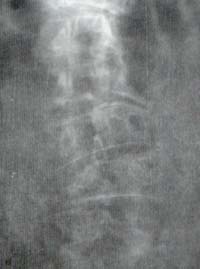

Figura 17. Espondilitis Deformans. Osteoartritis de columna lumbar. Se aprecian osteofitos gigantes formando puentes entre las vértebras